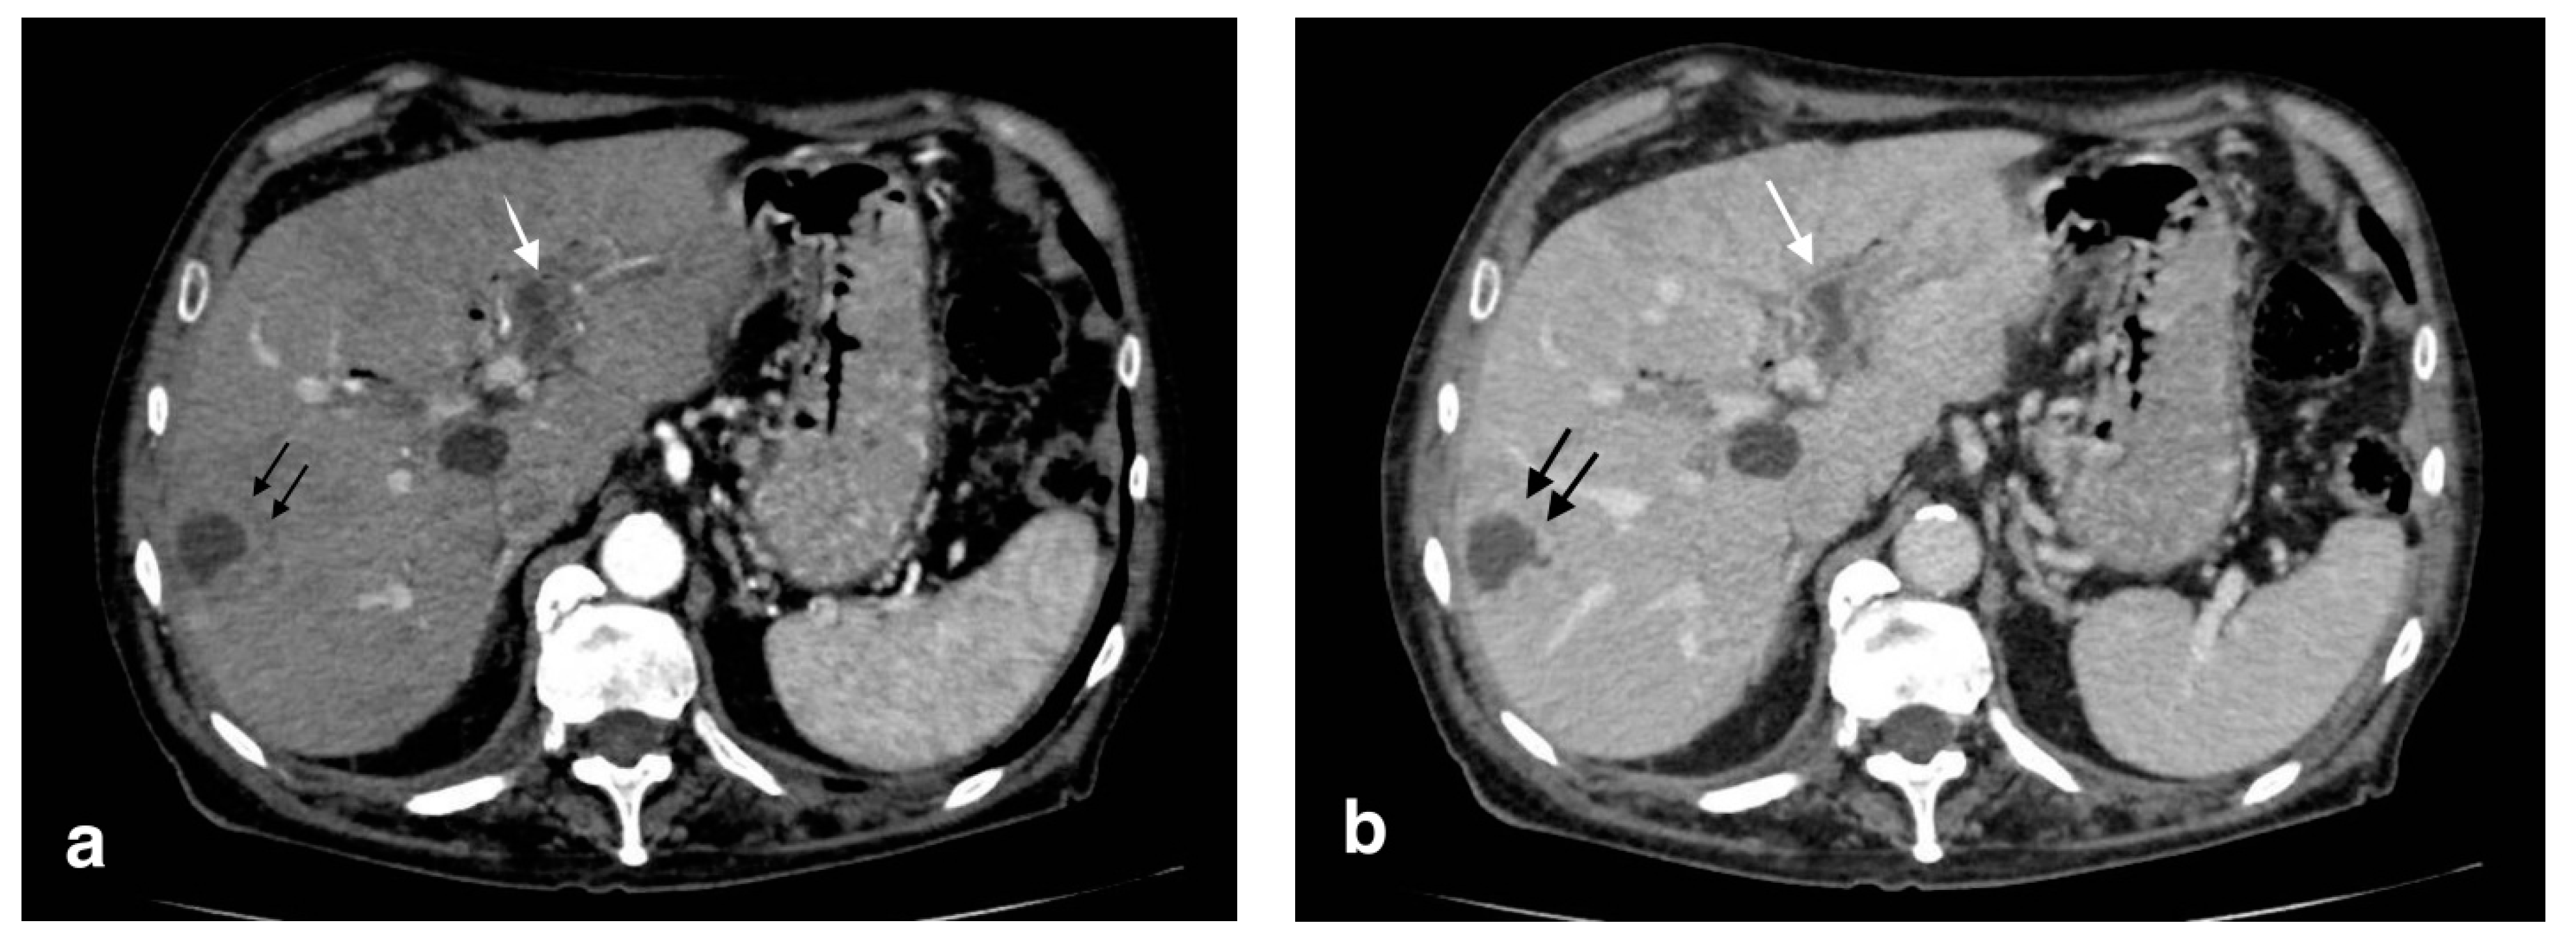

Figure 10.

Right portal vein thrombosis: extensive right portal vein hypodensity subsequent to an intraluminal thrombus formation (black arrows) with hepatic hyperemia (white arrows).

Figure 11.

Pylephlebitis in cholecystitis exacerbation: (a) massive thrombosis of the portal bifurcation with hyperdensity of portal walls due to pylephlebitis (white arrows) and inhomogeneous attenuation of liver parenchyma in arterial CT scan due to vascular occlusion; (b) axial scan: irregular thickening of cholecystic walls with contrast enhancement of liver parenchyma due to pericholecystic edema.